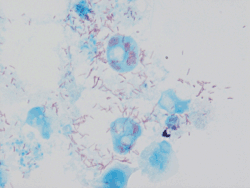

| Rickettsia conorii observed in Vero cells (red rods; magnification ×1,000)[1] | |

Rickettsia conorii is a Gram-negative, obligate intracellular bacterium of the genus Rickettsia that causes human disease called boutonneuse fever, Mediterranean spotted fever, Israeli tick typhus, Astrakhan spotted fever, Kenya tick typhus, Indian tick typhus, or other names that designate the locality of occurrence while having distinct clinical features.[3][4] It is a member of the spotted fever group and the most geographically dispersed species in the group, recognized in most of the regions bordering on the Mediterranean Sea and Black Sea, Israel, Kenya, and other parts of North, Central, and South Africa, and India.[3] The prevailing vector is the brown dog tick, Rhipicephalus sanguineus. The bacterium was isolated by Emile Brumpt in 1932[5] and named after A. Conor, who in collaboration with A. Bruch, provided the first description of boutonneuse fever in Tunisia in 1910.[6]